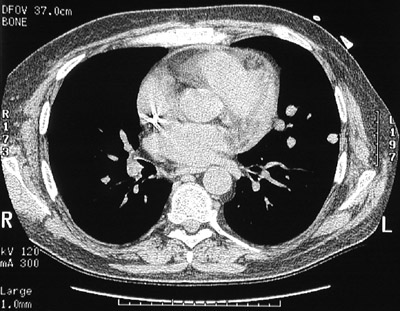

| There are scattered circumscribed nodules involving the lung parencyma in a patient who received an organ transplant. The nodules are seen above with high resolution chest CT scan and below with lung window (and the patient prone). A biopsy showed these lesions to be foci of post-transplantation lymphoproliferative disorder (PTLD). Immunosuppressive therapy creates an environment in which a lymphoid proliferation occurs that can resemble a lymphoma. The lesions often decrease or disappear if immunosuppression is diminished. |